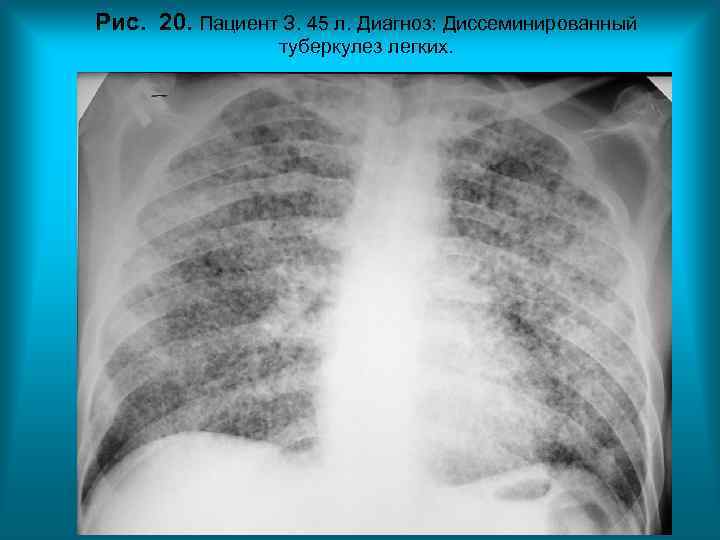

Рис. 20. Пациент З. 45 л. Диагноз: Диссеминированный туберкулез легких. Н. С. Воротынцева. С. С. Гольев Рентгенопульмонология